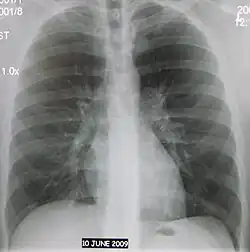

Флюорогра́фия органов грудной клетки — флюорографический метод рентгенодиагностики лёгких и органов грудной клетки, при котором рентгеновское изображение объекта переносится с флюоресцирующего экрана на фотоплёнку относительно небольших размеров. Применяют для выявления заболеваний органов грудной клетки, преимущественно при массовых обследованиях (скрининге). На снимке отчетливо видны искажения в плотности тканей легких. Места с повышенной плотностью сигнализируют о наличиях проблем.[1] По сравнению с рентгенографией эта методика требует меньших затрат, хотя и менее информативна.